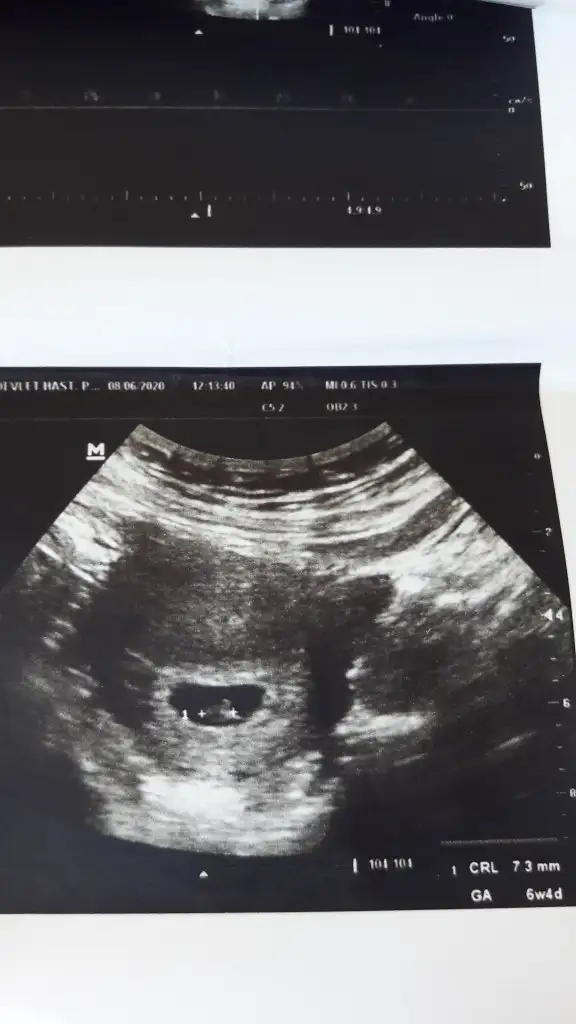

Erkek gibi geldi bana sizinkiKızlar 6+4 teki ultrason kağıdım kese bildiğin armut gibiydiYorumlayacak olan varmı?

Karından mı canımKizlar banada yorum yaparmisiniz rica etsem6+4 burda